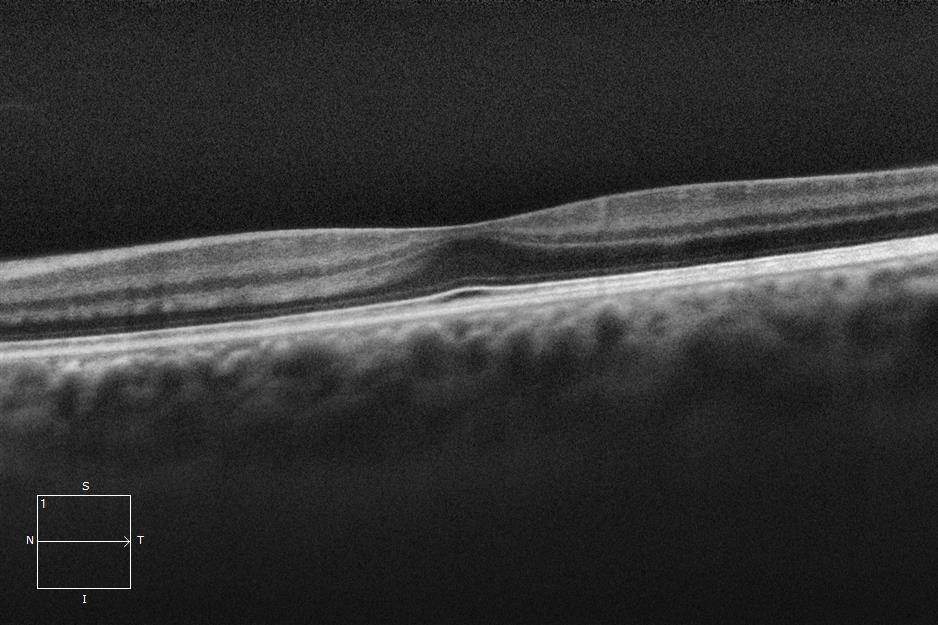

Three different patients with isolated grade 1 foveal hypoplasia. The definitions of fovea plana and foveal hypoplasia have led to controversy among experts. The term fovea plane refers to the anatomical absence of a foveal pit. An estimated 3% of children with clinically normal eyes have an underdeveloped foveal pit on OCT. According to some experts, a foveal pit is not absolutely necessary for foveal cone specialization. A diagnosis of fovea plana alone does not automatically herald functional disability. It is possible to maintain adequate visual acuity in an eye with a fovea plana. Foveal hypoplasia refers to an underdeveloped fovea with vision loss. Foveal hypoplasia has also been seen in conditions such as aniridia, albinism, achromatopsia, nanophthalmus, and incontinence. pigment and premature retinopathy.

In contrast to other definitions, Thomas et al. defined foveal hypoplasia as the persistence of inner retinal layers in the fovea and developed a grading system based on optical coherence tomography features. According to this grading system, grades 2, 3, and 4 of foveal hypoplasia corresponded to the fovea plana.

Grade 4 foveal hypoplasia represents grade 3, except that ONL expansion is not present in the fovea (called the fovea plana).